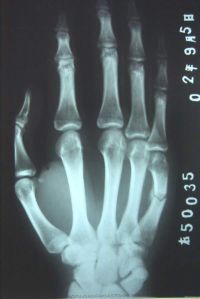

掌骨骨折

掌骨和腕骨关系。

掌骨